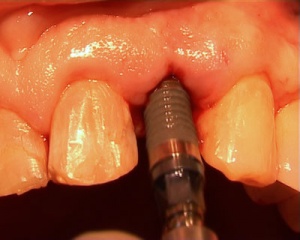

Un patient âgé de 60 ans présentant une incisive latérale supérieure gauche à extraire va bénéficier des derniers progrès issus des développements de logiciels de simulation: la chirurgie guidée.

Cette technique qui met en oeuvre un guide chirurgical très précis permet un gain de temps important, des suites opératoires réduites et une sécurité autorisant avec une grande fiabilité l'emploi des protocoles de mise en charge immédiate.